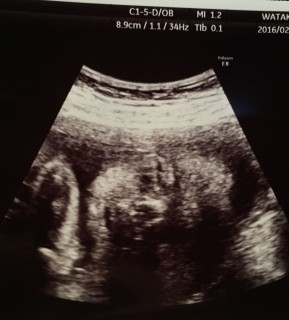

27w4d頭70.6㎜ お腹241.1㎜ 大腿骨51.7㎜ 体重1278.0g平均より1週大きめ。75gOGTT検査はクリアでき、ひと安心。(計7本も血液取るので案外と大変です。)逆子がなおり、前置胎盤も移動してきて、そしてなにより赤ちゃんが元気にすくすく育ってくれてます♪羊水過多ぎみで(^^;)胎動は感じにくいけど、それでもやっぱり主人の手のひらによく反応する赤ちゃんです。